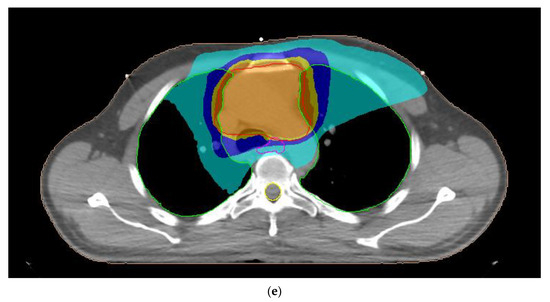

A typical dose distribution of a patient with thymoma from 3D-CRT, 7F-IMRT, 5F-IMRT, FA-VMAT and PA-VMAT plans is presented in Figure 1. The dose parameters for the PTV are summarized in Table 3. The mean TC, HI and CN for 3D-CRT were 58.4%, 1.11 and 0.48, respectively. The corresponding parameters for IMRT plans reached 95.6%, 1.06 and 0.83 whereas those for VMAT plans were up to 95.7%, 1.07 and 0.82.

Figure 1.

Typical dose distribution around the target volume, shown in red color, for (a) three-dimensional conformal radiotherapy, (b) seven-field intensity modulated radiation therapy, (c) five-field intensity modulated radiation therapy, (d) full-arc volumetric modulated arc therapy and (e) partial-arc volumetric modulated arc therapy techniques of a male patient with thymoma. The 95%, 90%, 75% and 45% isodoses are presented with orange, dark yellow, dark blue and light blue colors, respectively. The lungs, esophagus and spinal cord are denoted by the green, pink and yellow contours, respectively.